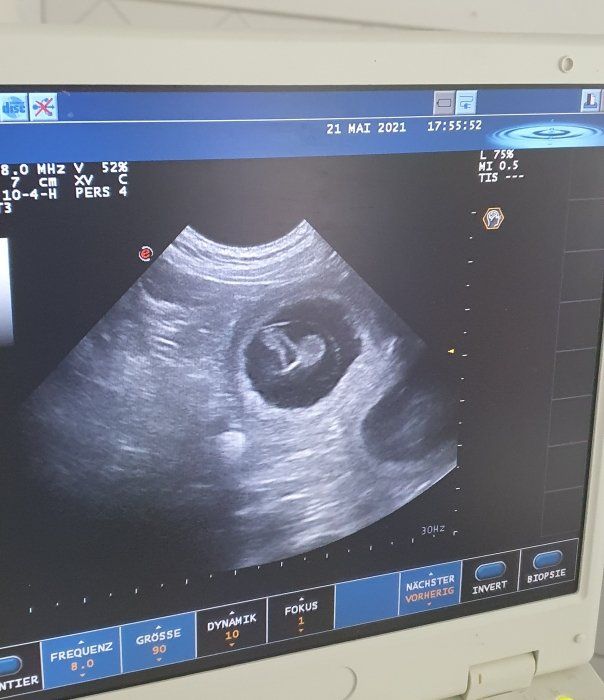

Jetzt, 27 Tage später, hebt unsere Tierärztin den Daumen 👍

Applecooki ist guter Hoffnung und eine spannende Reise nimmt an Fahrt auf.